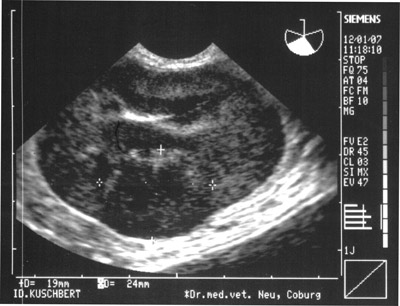

Hier kann man eine Katzenniere erkennen. Die Niere konnte mit einer Länge von 5.9 cm als zu groß angesprochen werden.

In der Nierenrinde befindet sich ein 19x24 mm großer Tumor (siehe Kreuze). Das Nierenbecken ist soweit noch o.B.

Die Blutwerte ließen keine Störung der Nierenleistung erkennen. Auf dem Röntgen ließ sich die Niere nur als „vergrößert“ ansprechen.